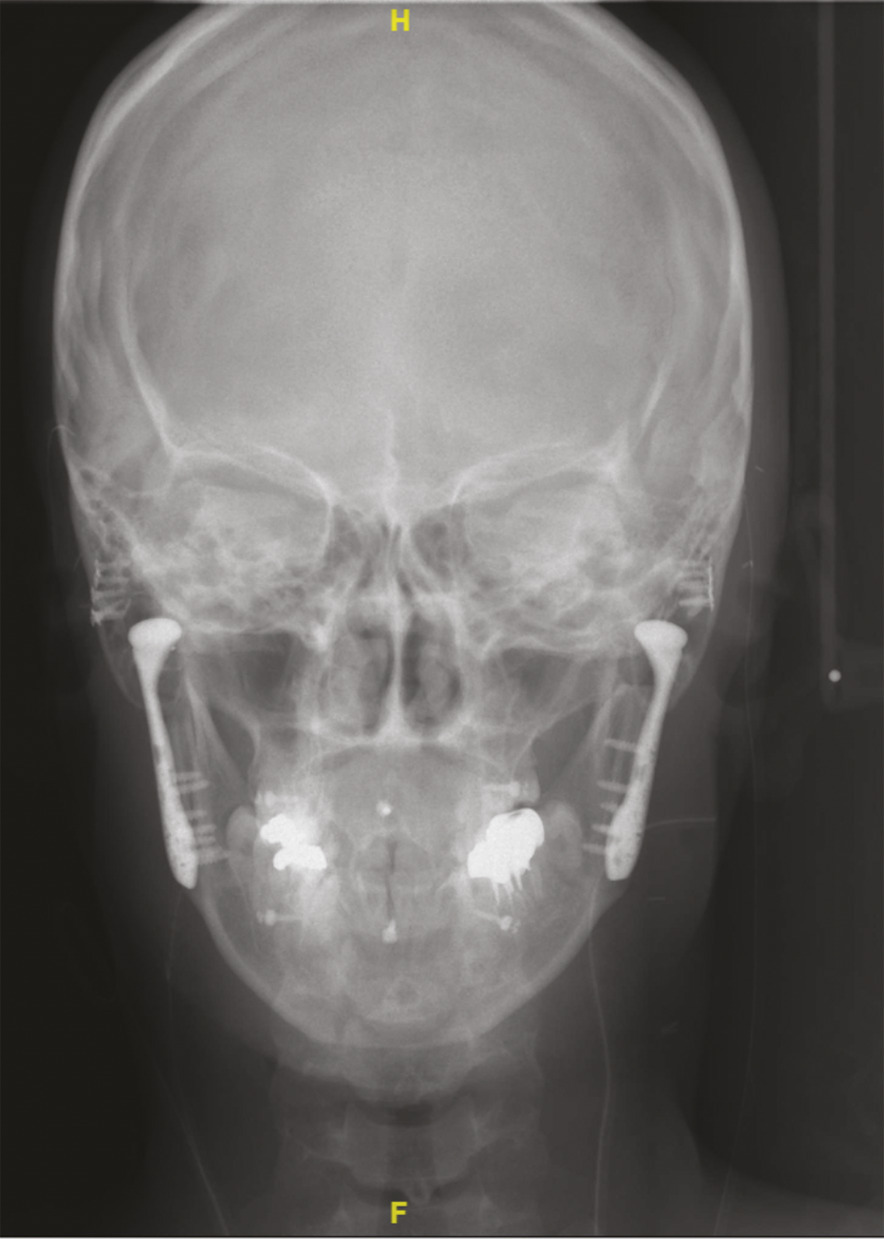

L’intervention se déroule sous anesthésie générale et la voie d’abord classique comporte deux incisions : l’une en avant du tragus et l’autre sous l’angle mandibulaire. Elle consiste dans un premier temps à réséquer le condyle pathologique (et si nécessaire le bloc d’ankylose associé). La prothèse est ensuite placée : l’implant temporal est fixé au niveau de l’arcade zygomatique, et l’implant condylien au niveau de la branche montante de la mandibule (fig. 3 ). Le remplacement peut concerner les deux articulations au cours de la même intervention. Le positionnement de l’implant doit être optimal afin d’obtenir l’ouverture buccale de 32 à 35 mm escomptée sans dislocation. L’amplitude des mouvements de la prothèse et l’occlusion dentaire doivent être vérifiées en fin d’intervention.

La durée d’hospitalisation varie de 2 à 5 jours et une antibiothérapie est habituellement prescrite pour une durée de 7 jours. Aucun blocage maxillo-mandibulaire n’est nécessaire en postopératoire. Une alimentation molle est recommandée pendant 1 mois (fig. 4) .